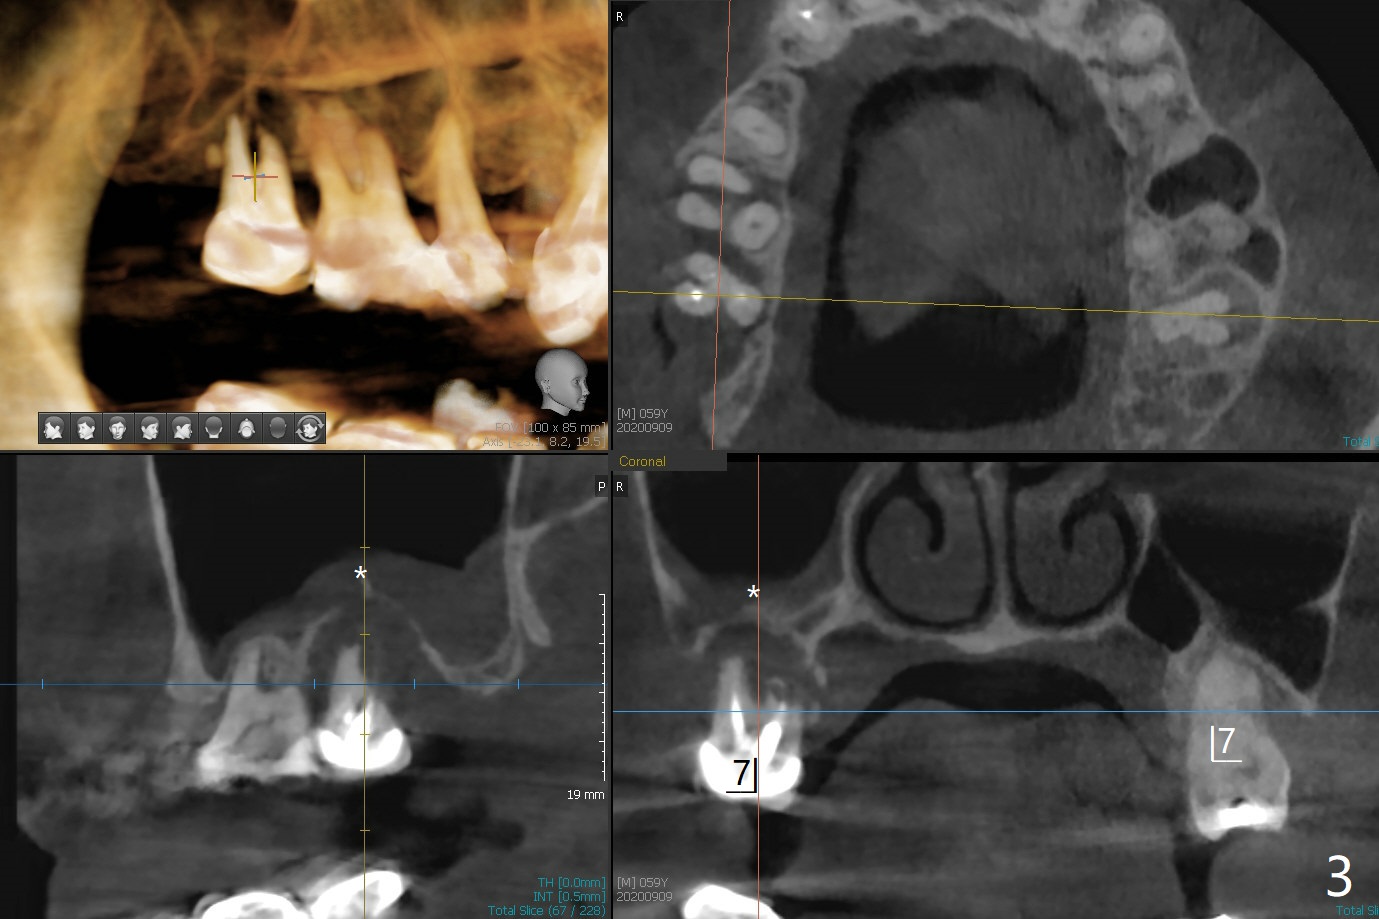

59岁女右上七骨质吸收严重(图一),上颌窦底板薄(图二:*),而窦膜厚(图三:*),应该容易提升,腭侧根吸收(图四:P),上颌窦底板穿孔(图五:*),拔牙后(图六:黑色),水提升(白箭头),放置PRF膜(黄色曲线)和粘性骨块(红色圆圈),最后完成位点保留(图七:大圆圈),放置另外一块PRF膜和6个月吸收膜,缝合,牙周或者树脂敷料。Return to No Deviation 19-21 位点保留后 导板与张口度 Xin Wei, DDS, PhD, MS 1st edition 09/09/2020, last revision 01/01/2021